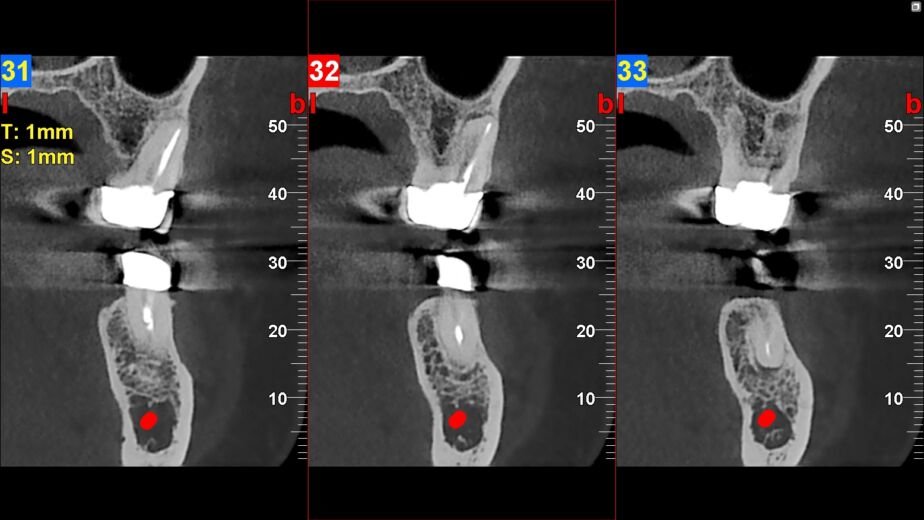

La tomografía computarizada de haz cónico (CBCT, por sus siglas en inglés) ha revolucionado la radiología facial al ofrecer imágenes tridimensionales de alta resolución con una dosis de radiación significativamente menor en comparación con las tomografías computarizadas convencionales. Este avance ha permitido a los médicos obtener una visión más clara y precisa de la anatomía facial, lo que resulta crucial para el diagnóstico y tratamiento de diversas afecciones. Por ejemplo, en odontología, el CBCT se utiliza para planificar implantes dentales, ya que proporciona información detallada sobre la densidad ósea y la ubicación de estructuras anatómicas importantes.

Además, el CBCT ha demostrado ser invaluable en la evaluación de trastornos maxilofaciales y en la planificación quirúrgica. Los cirujanos pueden utilizar estas imágenes para simular procedimientos antes de realizarlos, lo que reduce el riesgo de complicaciones y mejora los resultados postoperatorios. La capacidad de visualizar estructuras complejas en tres dimensiones ha cambiado radicalmente la forma en que se llevan a cabo las intervenciones quirúrgicas, permitiendo a los profesionales tomar decisiones más informadas y precisas.

La importancia de la radiología facial en el diagnóstico de fracturas y lesiones óseas

La radiología facial desempeña un papel crucial en el diagnóstico y tratamiento de fracturas y lesiones óseas. Las técnicas modernas permiten a los médicos identificar fracturas complejas que podrían pasar desapercibidas con métodos tradicionales. Por ejemplo, las radiografías digitales y el CBCT son herramientas valiosas para evaluar fracturas mandibulares o maxilares, proporcionando información detallada sobre la extensión del daño óseo.

Además, estas tecnologías permiten un seguimiento más efectivo del proceso de curación. Los médicos pueden comparar imágenes tomadas en diferentes momentos para evaluar cómo está sanando una fractura o si hay complicaciones asociadas. Esta capacidad para monitorear el progreso es fundamental para garantizar que los pacientes reciban el tratamiento adecuado y oportuno.